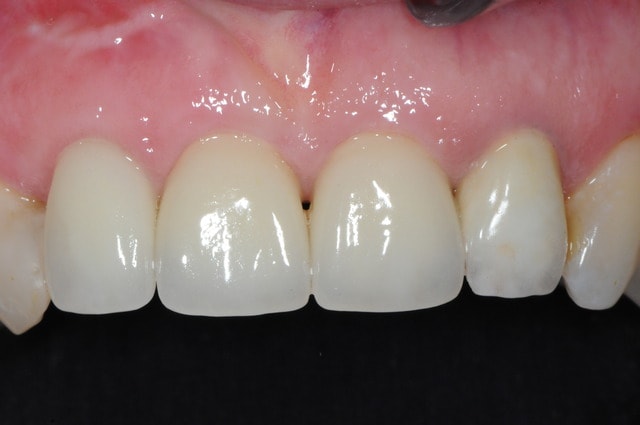

voici - voilà:

photo

1: j+ 2 ou 3 jours

2: j+8 mois

3-4-5: j+ 2 ans

sur la photo 3 on voit à la gencive que l'aspect est moins granité au niveau du col.

c'était ça l'indice pour trouver Charlie.